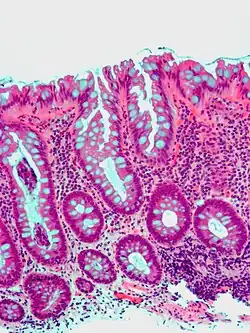

| Tubular adenoma | 2% at 1.5 cm[12] | Low to high grade dysplasia[13] | Over 75% of volume has tubular appearance.[14] |

|

| Tubulovillous adenoma | 20% to 25%[15] | 25–75% villous[14] |

| |

Traditional serrated adenoma. H&E stain. -